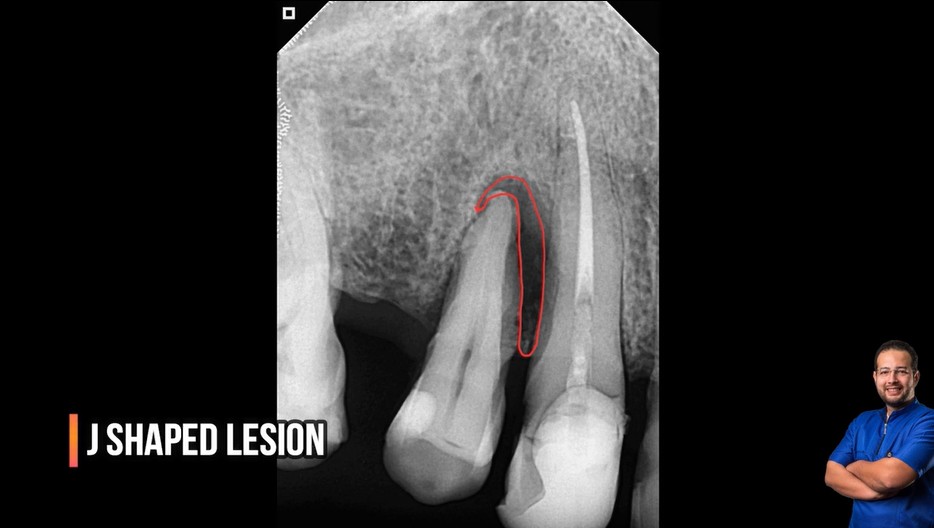

Treatment case sharing from dr wael